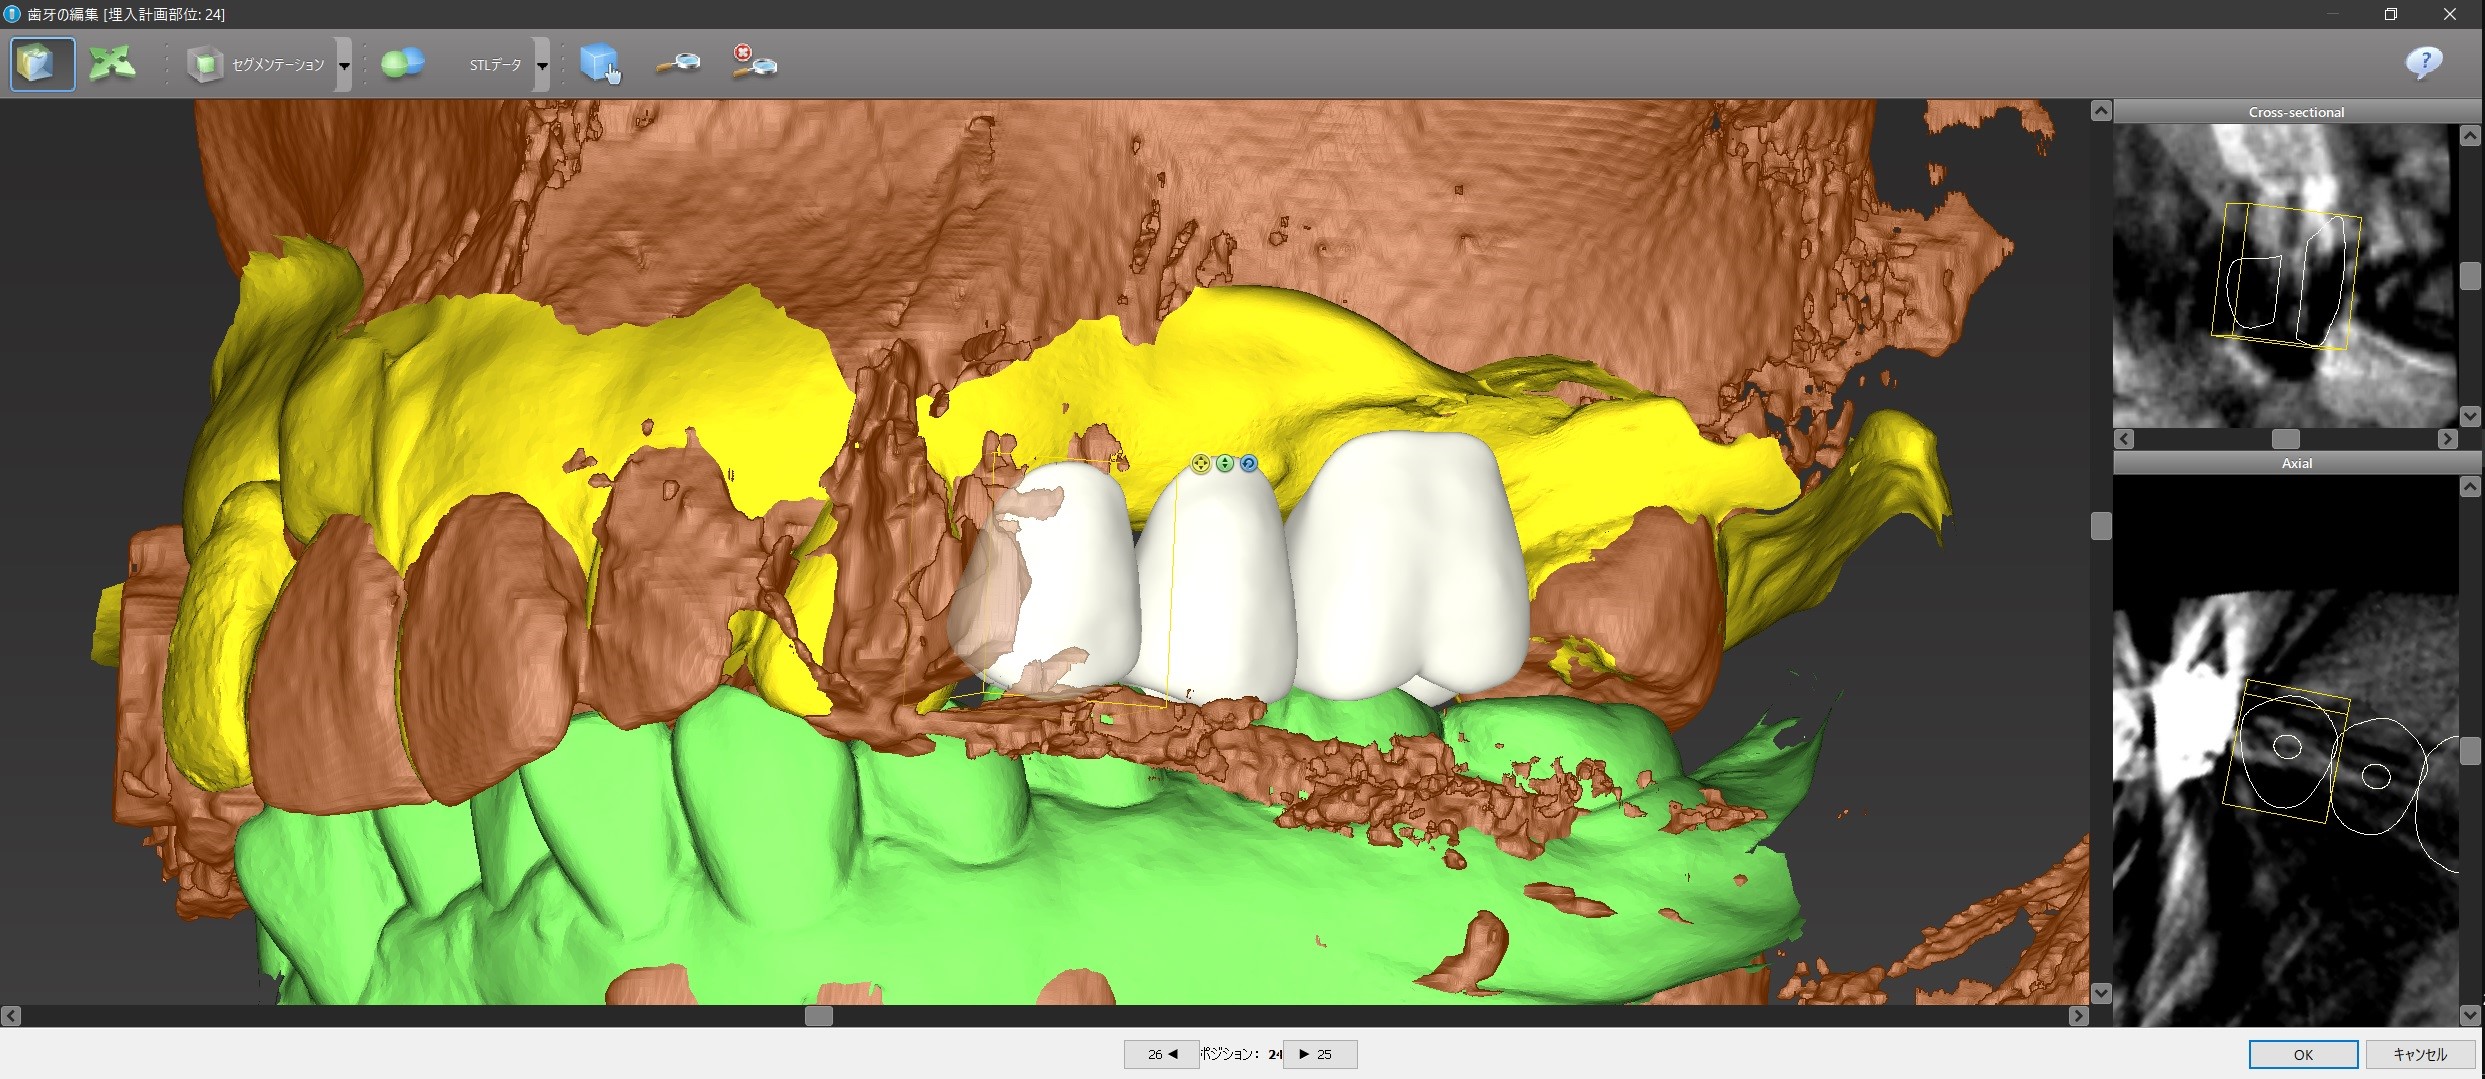

そのシュミレーション・ソフト上で、バーチャル・ティースを設計しました。

バーチャル・ティース

上下の歯のかみ合わせが分かりやすいように、CTの骨のデータの表示を消してバーチャル・ティースをカスタマイズします。

コンピュータ画面上で、下から見たり、裏から見たり、どアップで見て細かい調整をすることができます。

1本下の歯が内側に傾いているために、上下で噛み合わないヴァーチャル・ティースがあるのが分かります。

これが噛むようにするには、1本だけかなり内側にインプラント上の歯(「上部構造」といいます)を置かなければならならず、歯並びもおかしくなってしまうので、とりあえずこのヴァーチャル・ティースに合わせてインプラントをシュミレーションしてみます。